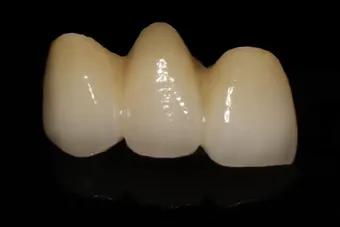

2.固定牙

固定牙通过调模缺牙两侧相邻的天然牙,将邻牙作为基牙,将多个牙套连接起来,通过粘接剂固定在两侧的天然牙上,像搭桥的方式一样,所以也被称为固定桥。

这种修复方式在曾经一段时间内恢复了很多缺牙患者的咀嚼问题,大受青睐。但多年后,随之而来的问题也逐步出现。固定牙最大的缺点是对天然牙的伤害,它需要把本是健康的牙齿人为磨小,而且因为固定牙本身需要相邻的天然牙作支撑,所承受的咀嚼压力会传递到相邻的天然牙上,长时间下来也容易出现邻牙问题,得不偿失。